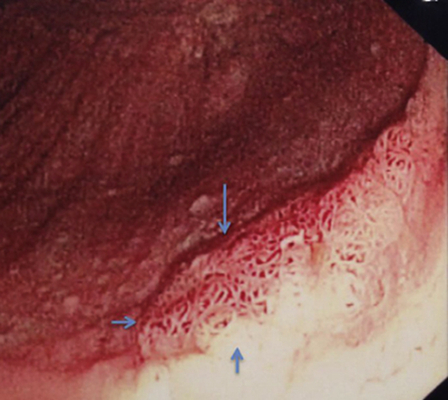

肛門癌圖片

肛癌早期症狀